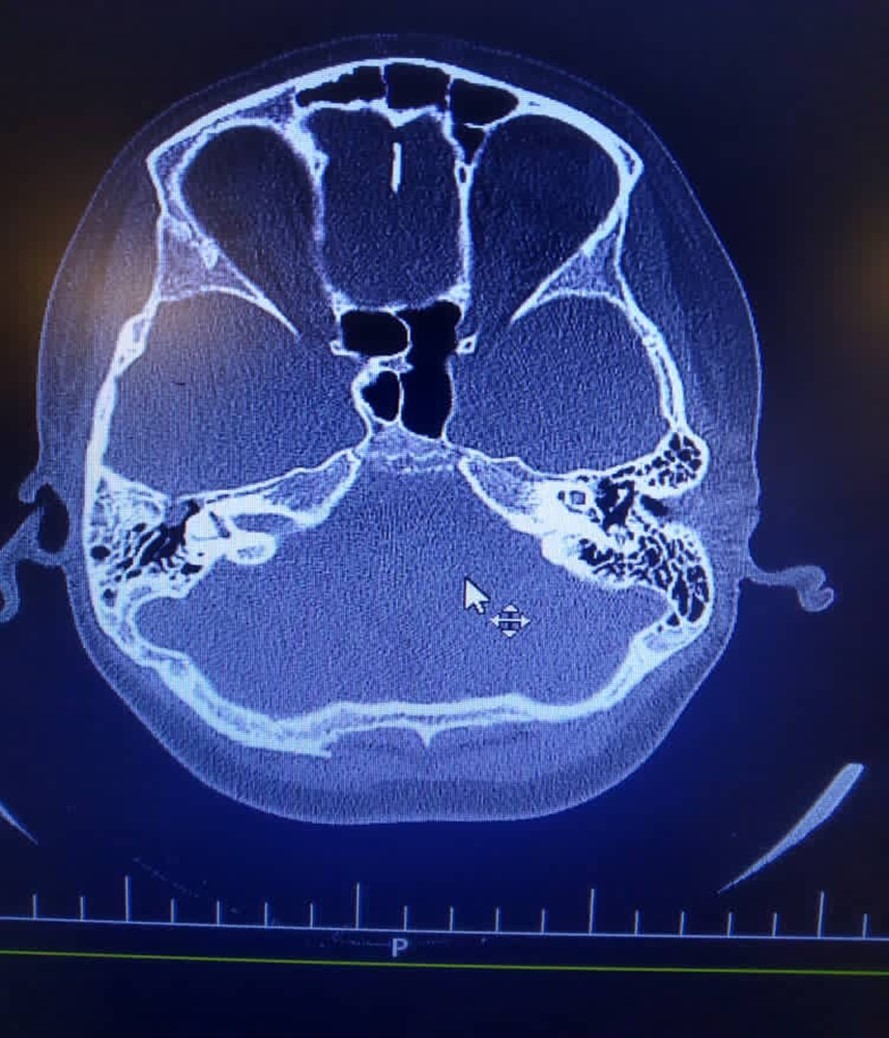

High dose of Cefotriaxone (100 mg/kg/day) and vancomycin (20mg/kg/q6h) were started. Dexamethasone (0.6 mg/kg/day), Phenytoin (5mg/kg/day/BD), Acyclovir (10mg/kg/dose/TDS) and pneumococcal vaccine, were added. He was clearly alert at second day of admission, and he was transferred to the pediatric ward at third day. His abdominal Sonography was normal. A fracture on the right roof of the right tympan and soft tissue density in the middle ear suggestive cholesteatoma reported in Brain Ct scan on day of admission (Figure 1).

Figure 1.There is evidence of fracture on the right roof of the right tympan. Slight opacity of right mastoid air cells is evident. There is soft tissue density in the middle ear and epitympan and preusak cavity suggestive cholesteatoma.